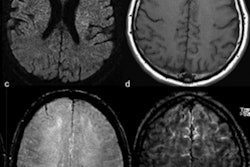

The Hyperfine POC MRI can be moved to the patient's bedside and uses power from a nearby wall outlet. The hospital is testing the device's effect on clinical workflow and is assessing its user interface and image quality. So far, the portable device has been used to perform 138 brain MRI exams of 123 patients with known brain pathology, including hemorrhages, ischemic stroke, hematomas, tumors, and edema.

To evaluate the scanner's performance, clinicians also are collecting anonymized images from standard MRI and CT scans of the same patients. Preliminary findings of the research are expected to be announced in early 2020.